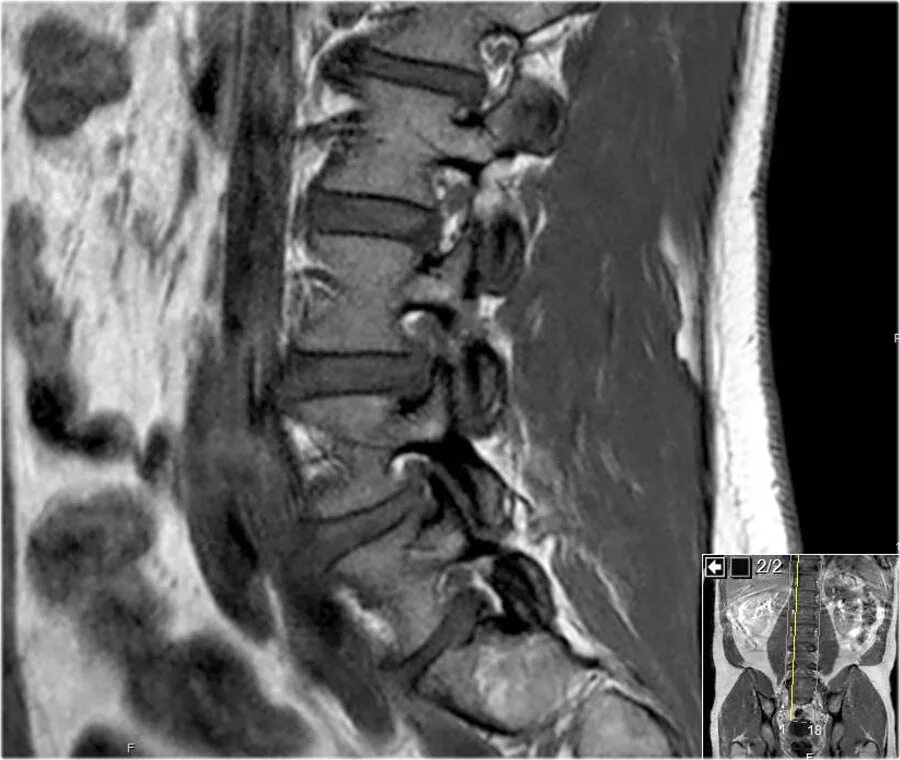

Грыжа диска 3